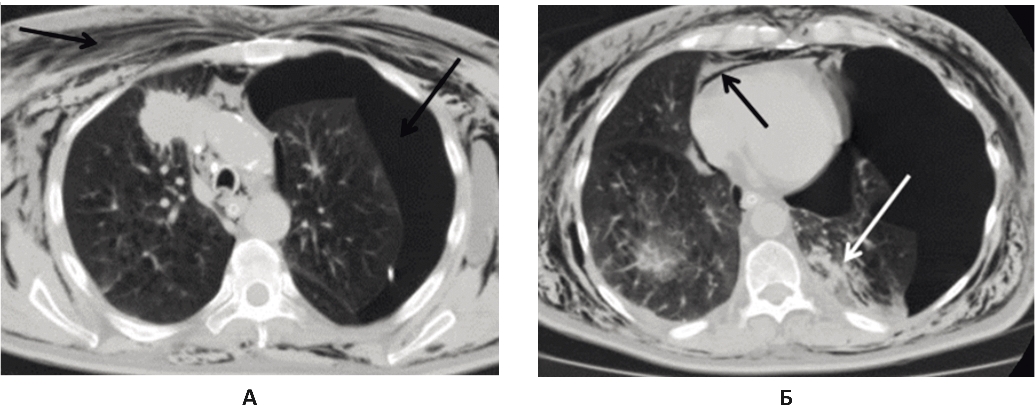

11.12.2017 г. у пациента одномоментно развилась массивная подкожная эмфизема грудной клетки, наросла дыхательная недостаточность, увеличился сброс воздуха по дренажу правой плевральной полости. Больной в экстренном порядке переведен в отделение реанимации. На КТ грудной клетки – тотальный пневмоторакс слева с полным коллабированием легкого, справа легкое практически расправлено (рис. 3). Выполнено экстренное дренирование левой плевральной полости. Продолжена активная аспирация воздуха из обеих плевральных полостей. В результате состояние пациента улучшилось, подкожная эмфизема уменьшилась, дыхательная недостаточность регрессировала. По дренажам обеих плевральных полостей наблюдался сброс воздуха: крупнокалиберный – справа, мелкокалиберный – слева. Наличие двусторонних бронхоплевральных свищей не позволило предпринять видеоторакоскопическое вмешательство, требующее раздельной интубации главных бронхов, поэтому была продолжена интенсивная терапия в условиях реанимации, санационная бронхоскопия.

Рис. 3. КТ грудной клетки от 11.12.2017 г., состояние после дренирования левой плевральной полости. А: в левой плевральной полости, в мягких тканях грудной клетки, в средостении визуализируется свободный воздух (черные стрелки); Б: компрессионные изменения нижней доли слева, небольшое количество жидкости в плевральных полостях (белая стрелка)

12.02.2017 г. состояние пациента стабильно тяжелое. На контрольной КТ грудной клетки отмечена положительная динамика. Слева легкое полностью расправилось, справа же сохранялся малый пневмоторакс. Сохранявшаяся межмышечная и подкожная эмфизема грудной клетки в динамике значительно уменьшилась. В базальных отделах легких стали заметны компрессионные и воспалительные изменения (рис. 4).

Рис. 4. КТ грудной клетки через 13 дней после поступления, состояние после дренирования правой и левой плевральных полостей. А: в плевральных полостях, в мягких тканях грудной клетки, в средостении сохраняется свободный воздух, справа количество воздуха наросло, слева значительно уменьшилось, пневмоторакс слева незначительно выражен в базальных отделах (черные стрелки); Б: сохраняются небольшое количество жидкости в плевральных полостях и компрессионные изменения в базальных отделах обоих легких (белая стрелка)